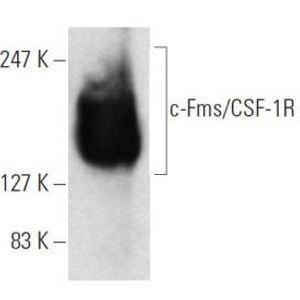

NOV 02, 2021Cell & Molecular BiologyDementia is an umbrella term for several age-related disorders that can cause cognitive problems such as dysfunction in ...